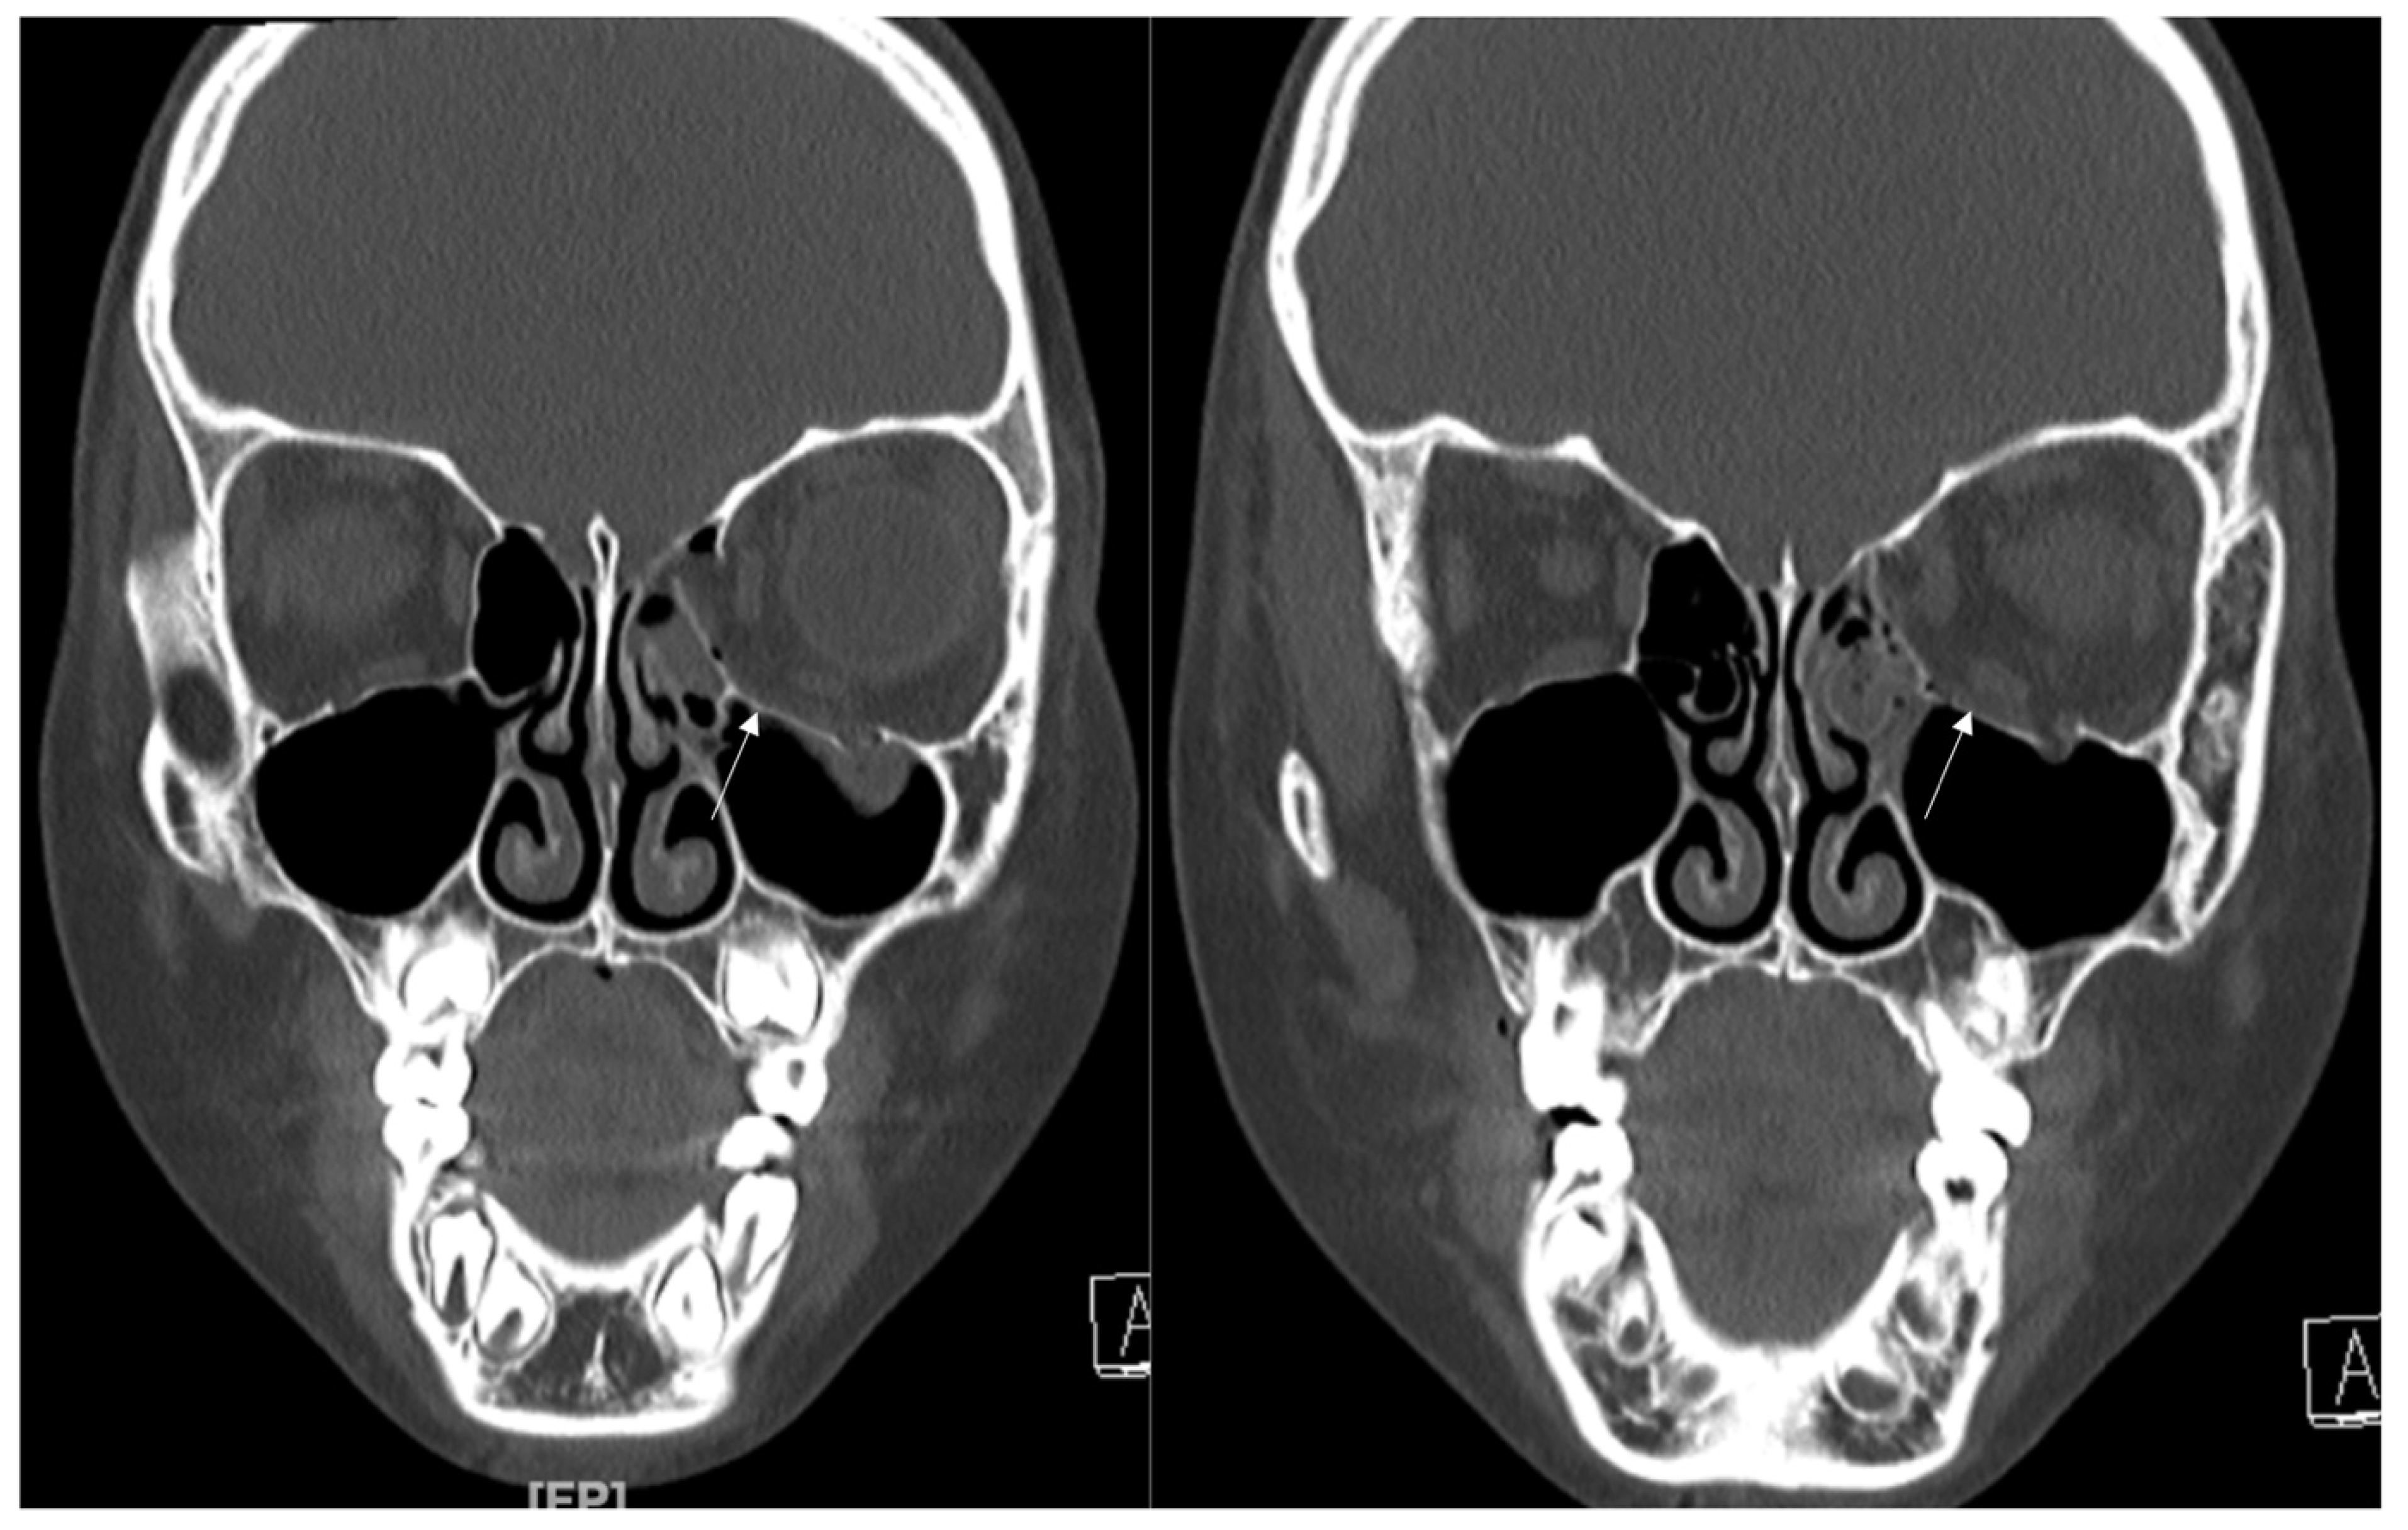

In this study, we excluded inferior wall fracture involving IOS. However, as shown in Figure 8, this inferior wall fracture with the involvement of IOS is also a good candidate for using titanium-reinforced porous polyethylene (TR-PPE) plates.

Figure 8. (A) A 29-year-old male patient came to our clinic with right eyeball swelling and ecchymosis caused by a direct trauma. The patient complained of pain and discomfort with eyeball movement. We surgically approached the inferomedial orbital wall fracture one day after the accident. After the subciliary incision, the fracture was exposed. (B) The titanium-reinforced porous polyethylene (TR-PPE) plate placed on the orbital floor using a single screw at the inferior orbital rim. The patient was discharged on postoperative day 2 with significantly improved pain and discomfort. The fracture sites were designated with white arrows. The titanium-reinforced porous polyethylene (TR-PPE) plate was placed on the inferomedial orbital wall using a single screw at the inferior orbital rim. (White arrow).